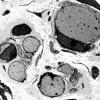

1B3 Fabry's Dz_011 - Copy

1B4 Fabry's Dz_013 - Copy

1B5 Fabry's Dz_006 - Copy copy

1B6 Fabry's Dz_025 - Copy

1B7 Fabry's Dz_028 - Copy

1B8 Fabry's Dz_005 - Copy